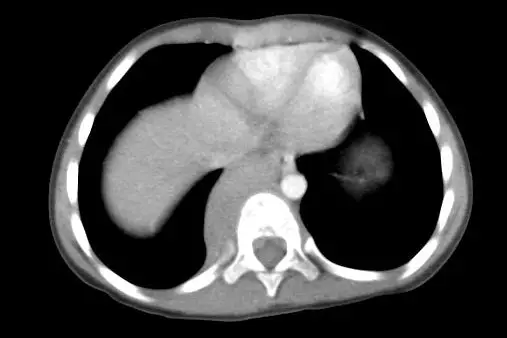

圖二(胸腹部 CT,軸向切面,疑似下胸段/腎上腺層次): CT 軸向切面顯示右側脊椎旁有一個明顯的均勻軟組織腫塊,緊鄰脊椎右側(paravertebral),邊界清楚,密度均勻,為後縱膈腔腫瘤的典型表現。腫塊位於後縱膈腔,符合來自交感神經節或周邊神經的腫瘤來源。肝臟及左側腎上腺/脾臟區域無明顯異常。此影像特徵高度支持神經性腫瘤的診斷。